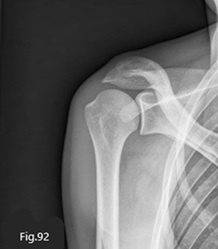

La radiographie ne montre aucune anomalie (Fig.92).